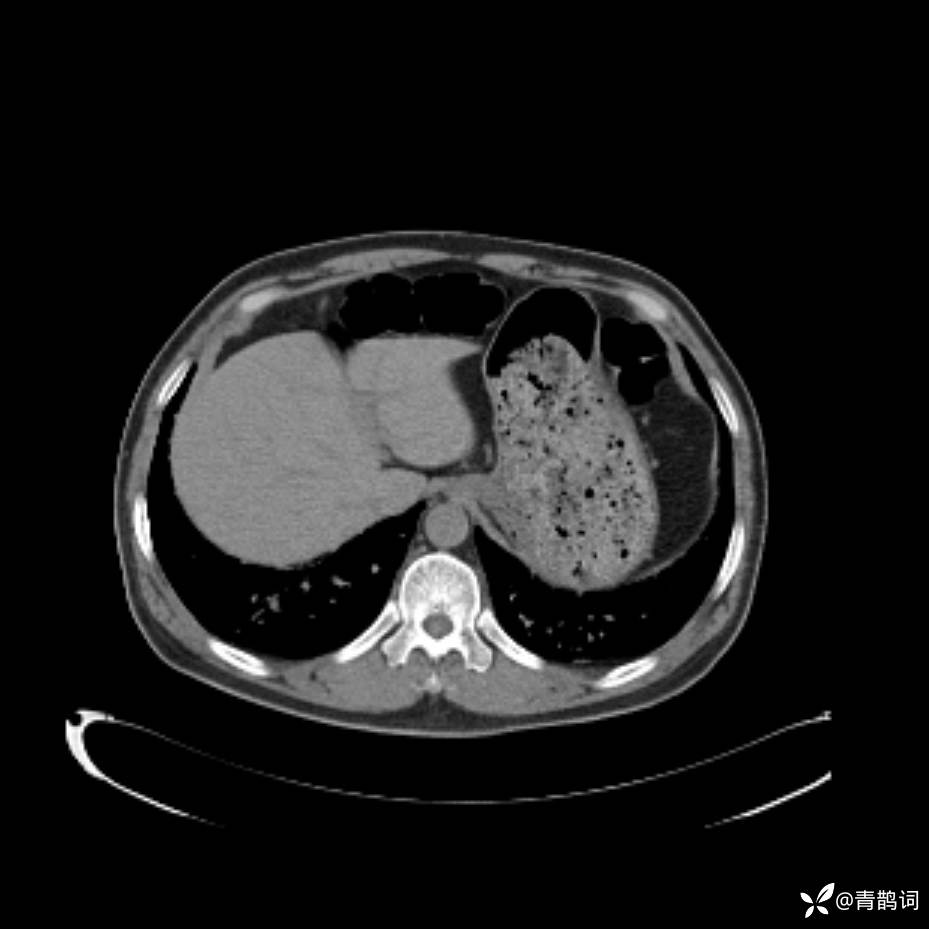

患者年龄:30岁。

患者性别:男。

简要病史:左颜面部肿胀2年,反复咳嗽咳痰,逐渐加重。

辅助检查